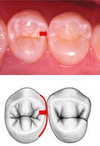

Mandibular buccal view: occlusal cervical crown dimension

Greater on mandibular 1st premolar

Mandibular buccal view: buccal cusp height

Greater on mandibular 1st premolar

Mandibular buccal view: buccal cusp sharpness

Greater on mandibular 1st premolar